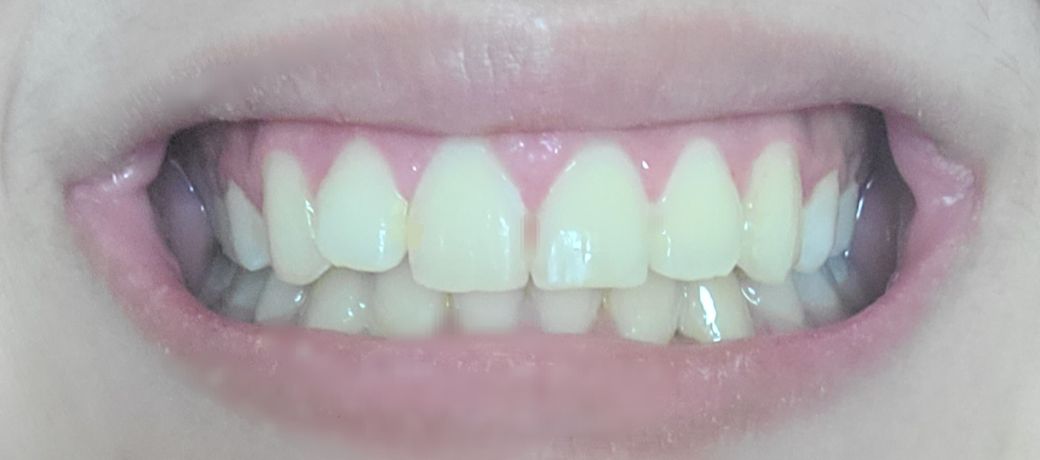

윗니 유지장치 안했는데 많이 휘었나요? (사진주의))

제가 교정하기 시작한건 3년전이고 작년 여름에 땠어요.

윗니는 고른편이고 아랫니가 심했어서 아래만 하려다가 위도 같이 하게 됐습니다. 때고 나서 아랫니는 고정된 유지장치를 했고 위는 빼고 끼는 유지장치로 받았습니다.

첫몇달은 잘끼고 다녔지만 불편하고 자주 까먹어서 이제는 전혀 안끼고 다닙니다^^... 손가락으로 치아를 문지르면 치아간의 차이는 약간 느껴지지만 개인적으로 외관상 봤을때는 다를게 없어보여요. 물론 제가 전문가가 아니라서 뭐라고 할수는 없고 제 게으름에 반성해야하지만...

• 1번 째 사진